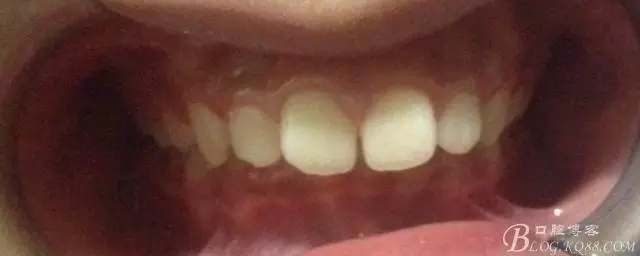

佩戴三個月的FR2, 效果奇佳!前牙基本達到淺覆蓋,淺覆合!接下來進入二期直絲弓固定正畸,排齊階段!

接下來盡管配合些雙側(cè)后牙對角牽引,咬合關(guān)系依,不盡人意。